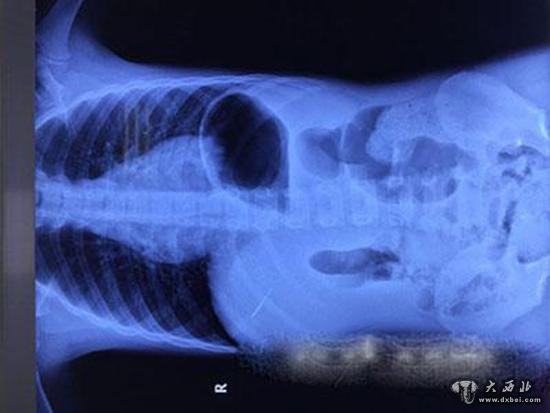

医生通过X光胸片在勇勇右腹部发现的针样金属物。

今年6月下旬,7岁的男孩勇勇因呼吸道感染来到苏州大学附属儿童医院就诊。没想到的是,本是一次普通的拍摄胸片检查,医生却有了意外的发现。医生在勇勇的右腹部发现了针样金属异物的存在。

那么金属异物究竟是何时进入勇勇体内,又是怎么进入的?勇勇的家长听到医生的描述后也很吃惊,并不知晓,因为勇勇一直以来身体很好,从未有过什么不适。为了追查金属异物的来源,家长拿来了还是勇勇约6年前,也就是大约15个月大时一次做X光线检查的胸片。更加令人吃惊的是,医生仔细对比了前后两张胸片后,发现早在勇勇15个月大时金属异样物就已存在。“因为15个月大时拍的胸片的位置问题,加上那时胸片曝光过白,不仔细看确实很难发现。”勇勇的主治医生苏州大学附属儿童医院普外科医生朱杰说。